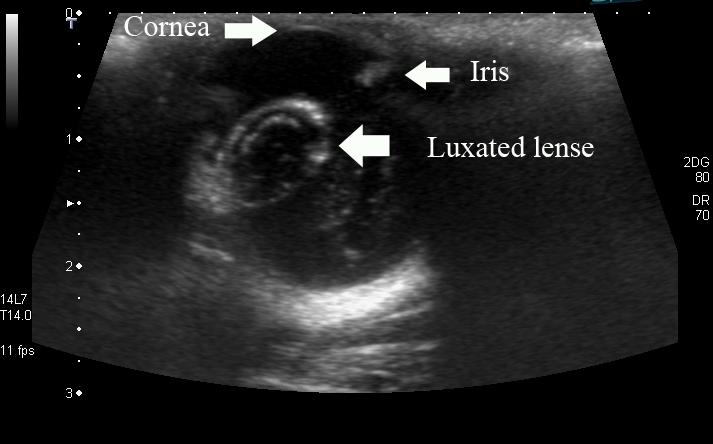

lens luxation?